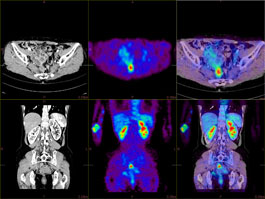

FUSION VIEWER

The PET/CT Fusion protocol provides flexible and simple image overlay analysis. Standard Uptake Value calculations are enabled with ROIs and VOIs.

MULTI-MODALITY FUSION

Up to four different series from different phases or even modalities can be layered using varied opacity profiles.